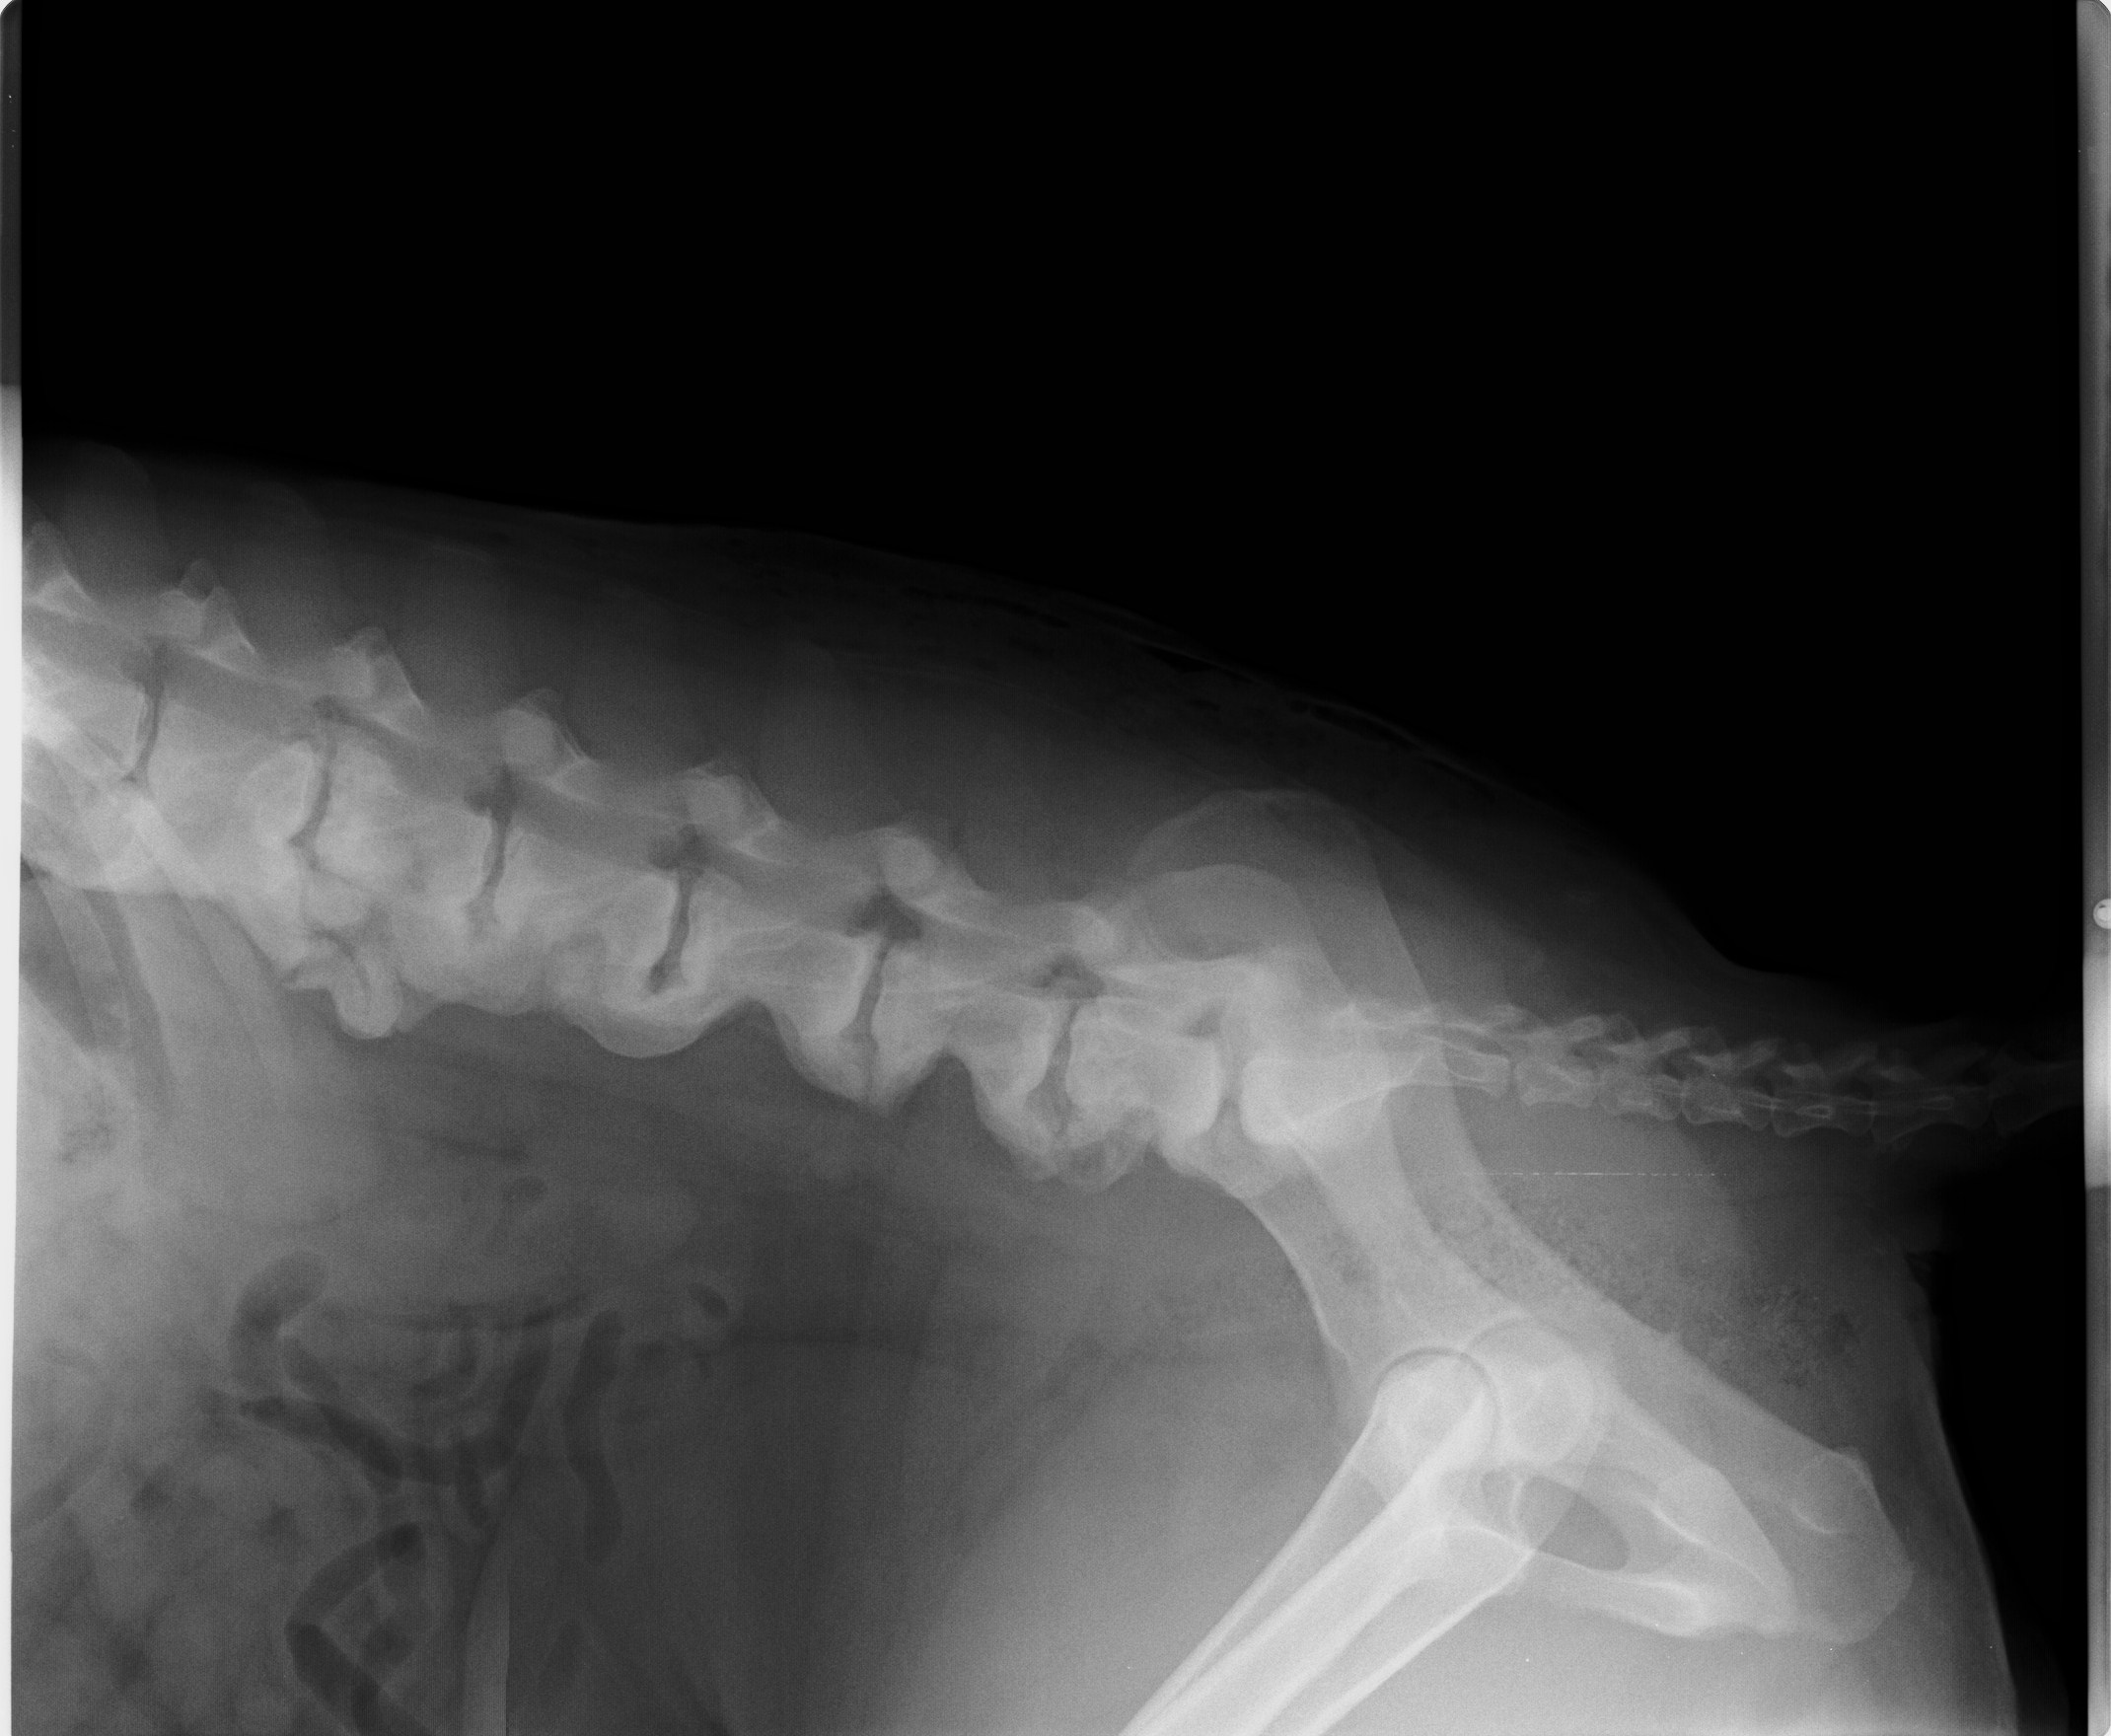

Akira, narodená cca február 2009, sa našla pri Lehniciach. V tejto lokalite je to už za posledný pol rok asi piata akita, takže je evidentné, že sa ich nejaký množiteľ zbavuje! Akira je dokonalou predstaviteľkou plemena americká akita. Má za sebou neľahké obdobie, prešla to totiž operáciou vyskočenej platničky, ktorej predchádzal život v krutých bolestiach :( Platnička je opäť na mieste, ale Akira má problém s celou chrbticou, ktorá je zrastená (prikladáme RTG snímky). Akira sa teda bude musieť doživotne šetriť, aby nemala zbytočné bolesti. To znamená kontrolovaný pohyb, určite nenechávať niekde na dvore bez dozoru, aby celý deň lietala! Prechádzky iba na vodítku, kľudne na dlhom, ale treba dať pozor aby nezabehla a nezačala sa hrať na naháňačku. Skákanie minimalizovať ako sa len bude dať, a ideálne žiadne schody! Akira si túto starostlivosť ale veľmi zaslúži :) Je to neopísateľný miláčik, lásky má na rozdávanie aj za troch. Miluje ľudí, úplne každého človeka zbožňuje, aj toho, ktorého ešte nepozná :) Na klinike si ju celý personál zamiloval a ona sa túlila ku každému. Akiru nám dokonale opísal pán doktor na klinike, ktorý povedal, že "je to miláčik, ale jadrový fyzik to nie je" :D Toto Akiru dokonale vystihuje ale to samozrejme neznamená, že sa nič nedokáže naučiť, len z nej nikdy nebude komisár Rex a ani Hatchiko :D Je to také milé trdielko, ktoré nechce nič iné, ako milovať a byť milovaná. Je nenáročná, nekonfliktná, znášanlivá so psíkmi aj fenkami, jednoducho dokonalá. Hľadá si rodinu, ktorá jej bude vedieť zabezpečiť potrebnú opateru a starostlivosť. Samozrejme konzultácia novej rodiny s ortopédom je možná. Akira čaká na svoju druhú šancu od februára 2017.

Akira, geboren ca. im Februar 2009, wurde in Lehnice gefunden. In dieser Umgebung ist das schon fünfte Akita in den letzten 6 Monaten, also offensichtlich werden die von ein Vehrmehrer rausgeschmissen. Akira ist typischer Darsteller von Amerikanische Akita. Sie hat schwere Zeiten hinter sich. Sie hat große Schmerzen im Rücken gehabt, ihre Bandscheibe wurde operiert. Bandwechsel ist wieder auf seinem Platz, aber Akira hat Problem mit dem ganzen Rückgrat (die RTG Bilder legen wir bei). Akira muss sich den Rest des Lebens schonen, damit sie keine unnötigen Schmerzen hat. Das heißt die Bewegung unter Kontrolle zu halten, kein freies Laufen am Hof ohne Aufsicht. Die Spaziergänge nur an der Leine, auch auf längeren, nur man muss aufpassen dass sie nicht laufen will. Springen muss so viel es geht minimalisiert, ideal keine Treppen. Akira verdient sich diese Sorgfalt :) Sie ist ein unbeschreibliches Liebling, Liebe kann sie für drei verschenken. Sie liebt sehr alle Menschen, sogar auch Fremde :) In der Klinik hat sie das ganze Personal geliebt. Akira wurde von Hr. Doktor so beschrieben: „sie ist ein Liebling, kein Kernphysiker“ Das heißt aber nicht, dass sie nichts lernen kann, aus ihr wird nur kein Kommissar Rex und kein Hatchiko werden. Sie ist so lieb und das einzige was sie will ist geliebt zu werden und jemanden zu lieben. Sie ist nicht anspruchsvoll, konfliktlos, erträgt sich mit anderen Hunden, einfach vollkommen! Sie sucht eine Familie die ihr die notwendige Versorgung geben kann. Selbstverständlich sind weitere Konsultationen mit einem Orthopäden möglich. Akira wartet auf ihre zweite Chance seit Februar 2017.